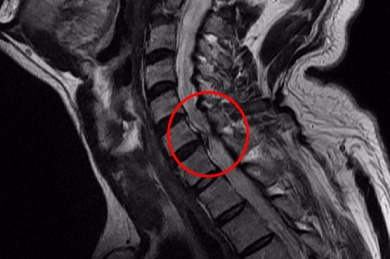

척수라는 중추 신경은 목뼈를 통과해 목 아래 감각과 운동 신경에 영향을 끼치기 때문에 목 디스크 증상들이 나타나면 신속하고 빠른 대처가 필요해요. 목디스크 치료형식으로 주로 초기 스탭에는 물리치료나 약물을 통해 대개의 환자들이 호전돼요. 그렇지 않다고 하면 신경 성형술과 차단술이라고 부르는 뼈주사 목디스크 치료방법을 이용하는데, 이 치료방법은 통증이 있는 신경 부위에 약물을 삽입하는 것입니다.

시술로써 눈에 띄게 질환을 현저히 치료하시는 것이 아니라 염증을 보완하고 통증을 낮추는 것이 포인트입니다. 이러한 방식으로 비 수술적인 치료를 3개월 이상 넘었음에도 불구하며 증상이 호전을 보이지 않으신다면 목디스크 치료방법 중 수술적 치료를 고심해야 하더라고요. 인공디스크를 투입하기 위함으로 절개를 통하기에 디스크를 제거하며 뼈를 하나로 유합 시켜서하는 것과, 내시경 수술로 빠져 나온 수핵 자체만을 제거시켜서하는 방법이 있다고하고요.